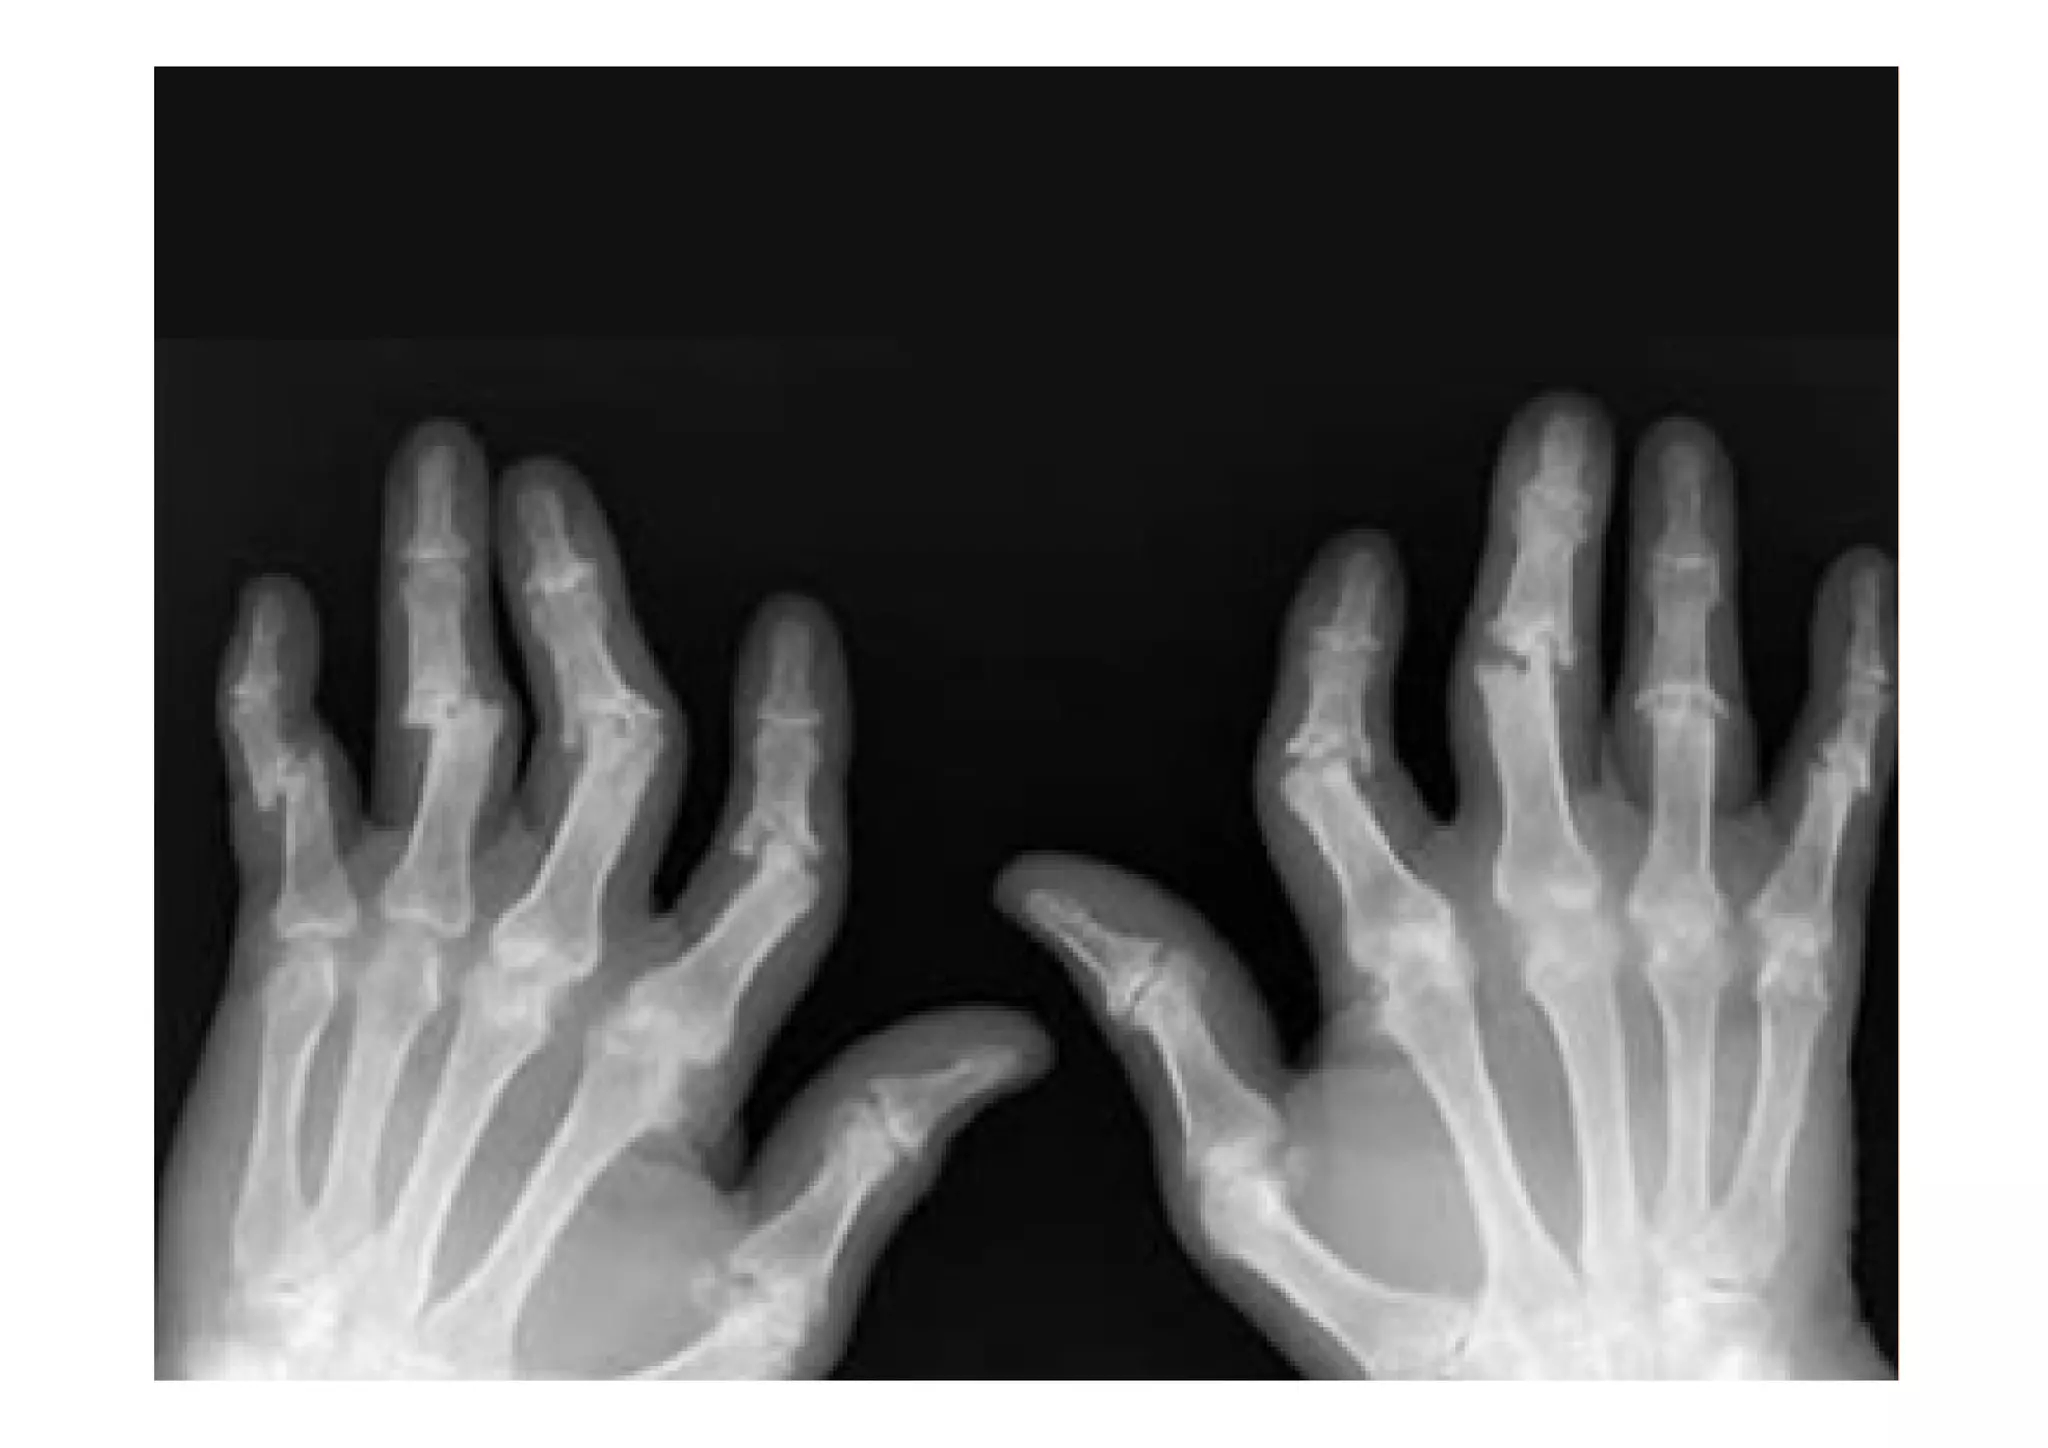

ARTROPATÍA PSORIÁSICA

Diferentes patrones:

Oligoartritis asimétrica

Poliartritis simétrica parecida a AR (FR neg)

Afectación IFD (onicopatia)

Artritis mutilante

Afectación axial tipo EA

Características generales

Rigidez matutina

Afectación ungueal

Dolor articular

Entesitis

Dactilitis (dedos en salchicha)

Síntomas constitucionales